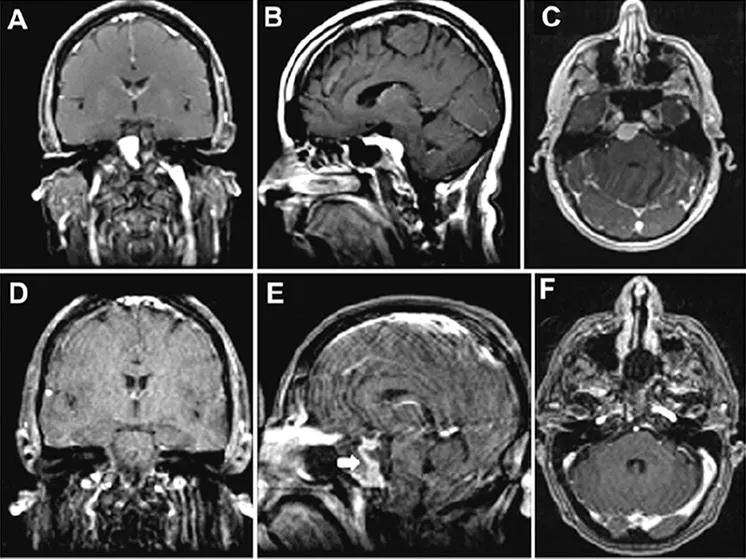

52岁女性患者,表现为复视及间歇性头痛。体检发现右眼外展功能受损。MRI显示右岩斜交界处肿块均匀强化,伴广泛斜坡附着,提示脑膜瘤(图A-C)。行部分岩尖切除术。术后MRI证实肿瘤全切(图D-E),无脑组织损伤。注:采用增强鼻中隔皮瓣进行重建。患者术后第7天出现脑脊液漏,手术检查发现由鼻中隔皮瓣右上角移位引起,但移位已成功永久矫正。患者术后恢复良好,复视消失,外展功能恢复正常。

图示:术前图像显示起源于上斜坡的岩斜脑膜瘤。肿瘤均匀强化,脑干受压,无海绵窦侵犯。术后图像显示肿瘤完全切除。E:图中白色箭头示血供保留的增强重建鼻中隔。